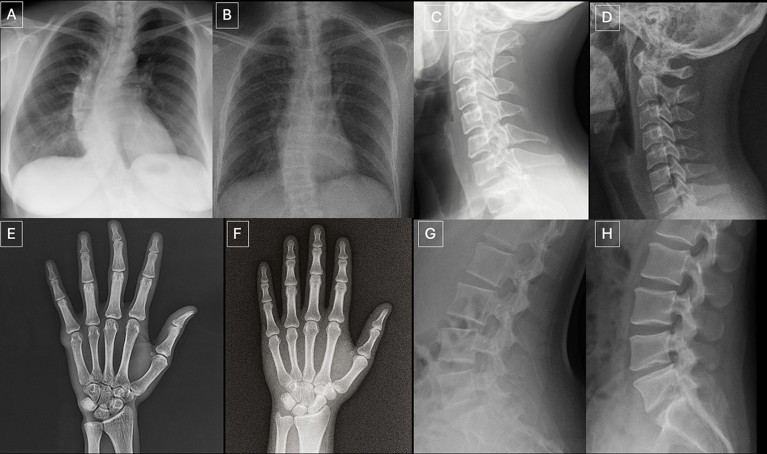

AI-generated X-rays, such as these examples, could distort AI tools used to analyse medical data if included in their training data sets.Credit: Radiological Society of North America (RSNA)

Real X-ray images of different body parts are on the left, AI-generated X-rays are on the right. Can you spot the difference?Credit: Radiological Society of North America (RSNA)